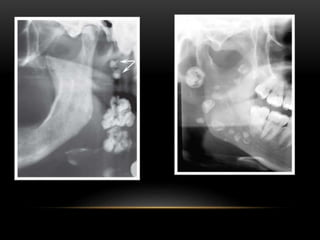

A. RIGHT SIDE OF AN OPG SHOWING A LARGE RADIOPACITY IN THE

LOWER PREMOLAR REGION (ARROWED).

B. LOWER 90° OCCLUSAL OF THE SAME PATIENT SHOWING THE

OPACITY TO BE A LARGE STONE IN THE RIGHT SUBMANDIBULAR

DUCT